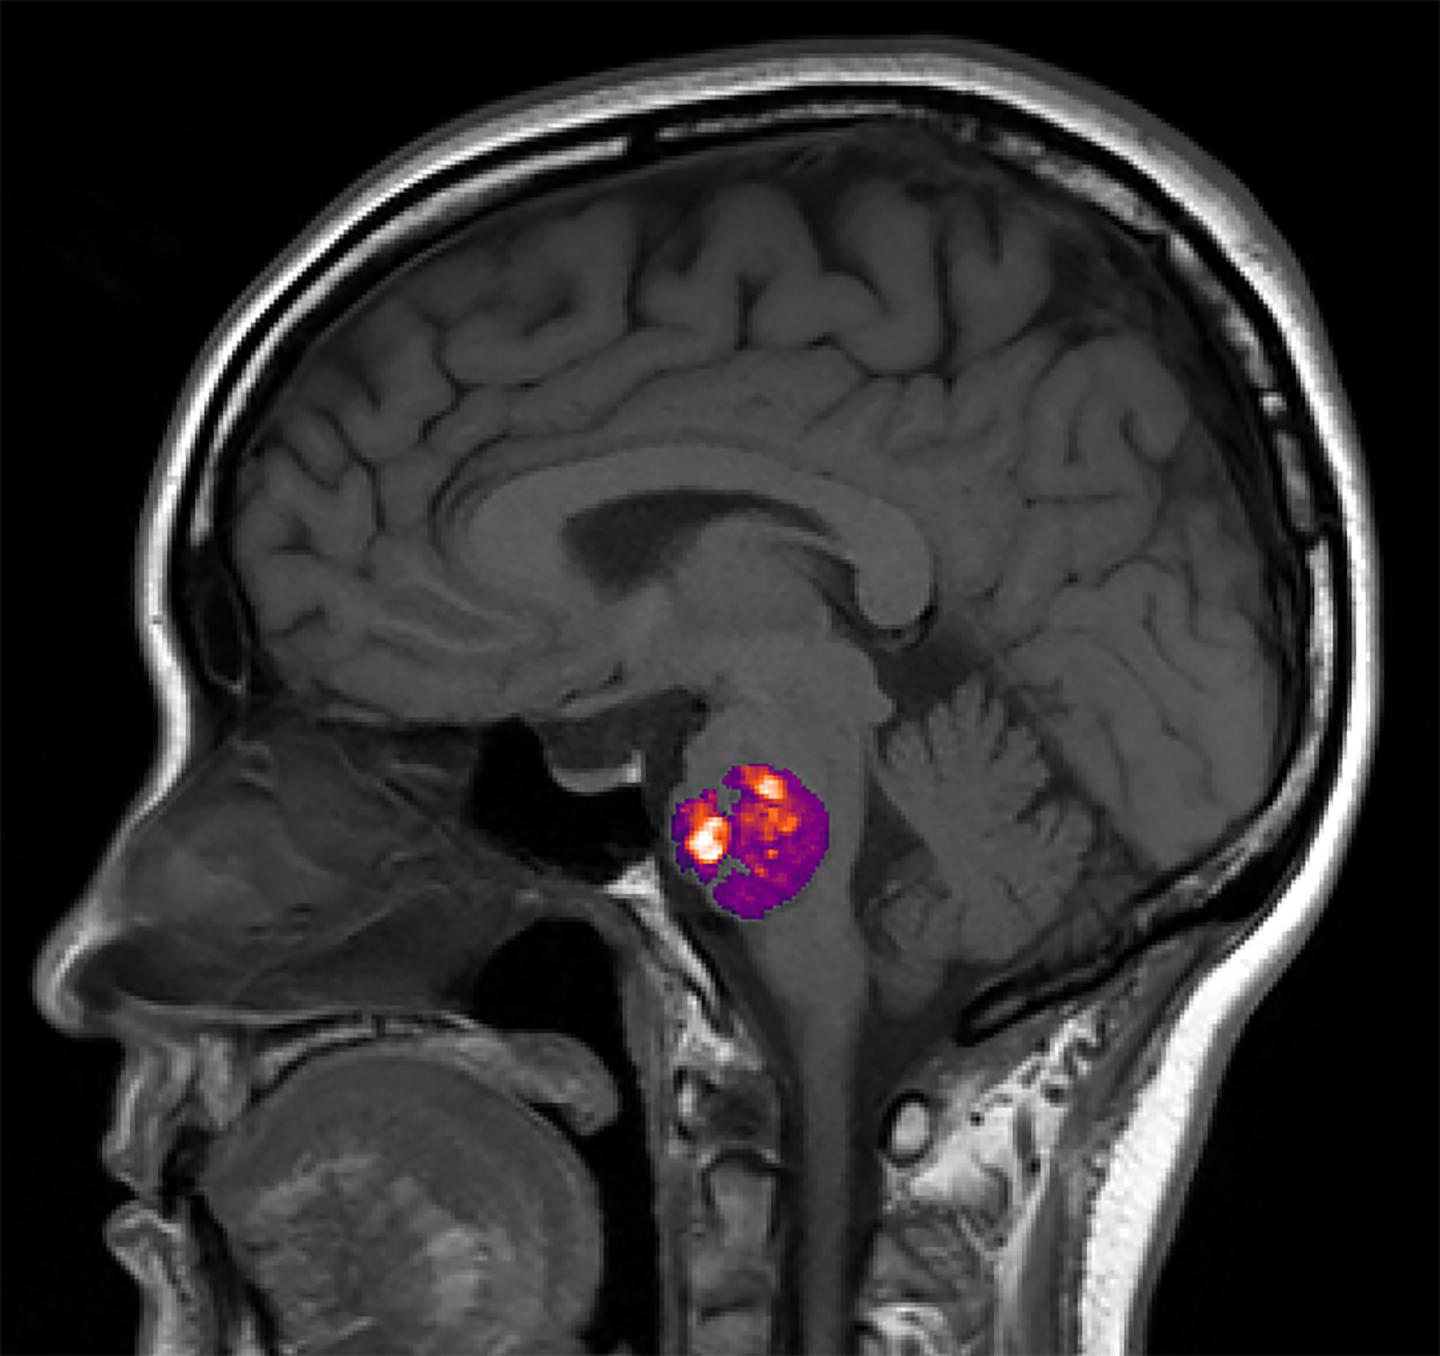

image: An NIH funded study found a link between the appearance of abnormal, stroke-inducing blood vessel bundles, called cavernous angiomas, and the composition of a person's gut bacteria.

In a nationwide study, NIH funded researchers found that the presence of abnormal bundles of brittle blood vessels in the brain or spinal cord, called cavernous angiomas (CA), are linked to the composition of a person's gut bacteria. Also known as cerebral cavernous malformations, these lesions which contain slow moving or stagnant blood, can often cause hemorrhagic strokes, seizures, or headaches. Current treatment involves surgical removal of lesions when it is safe to do so. Previous studies in mice and a small number of patients suggested a link between CA and gut bacteria. This study is the first to examine the role the gut microbiome may play in a larger population of CA patients.